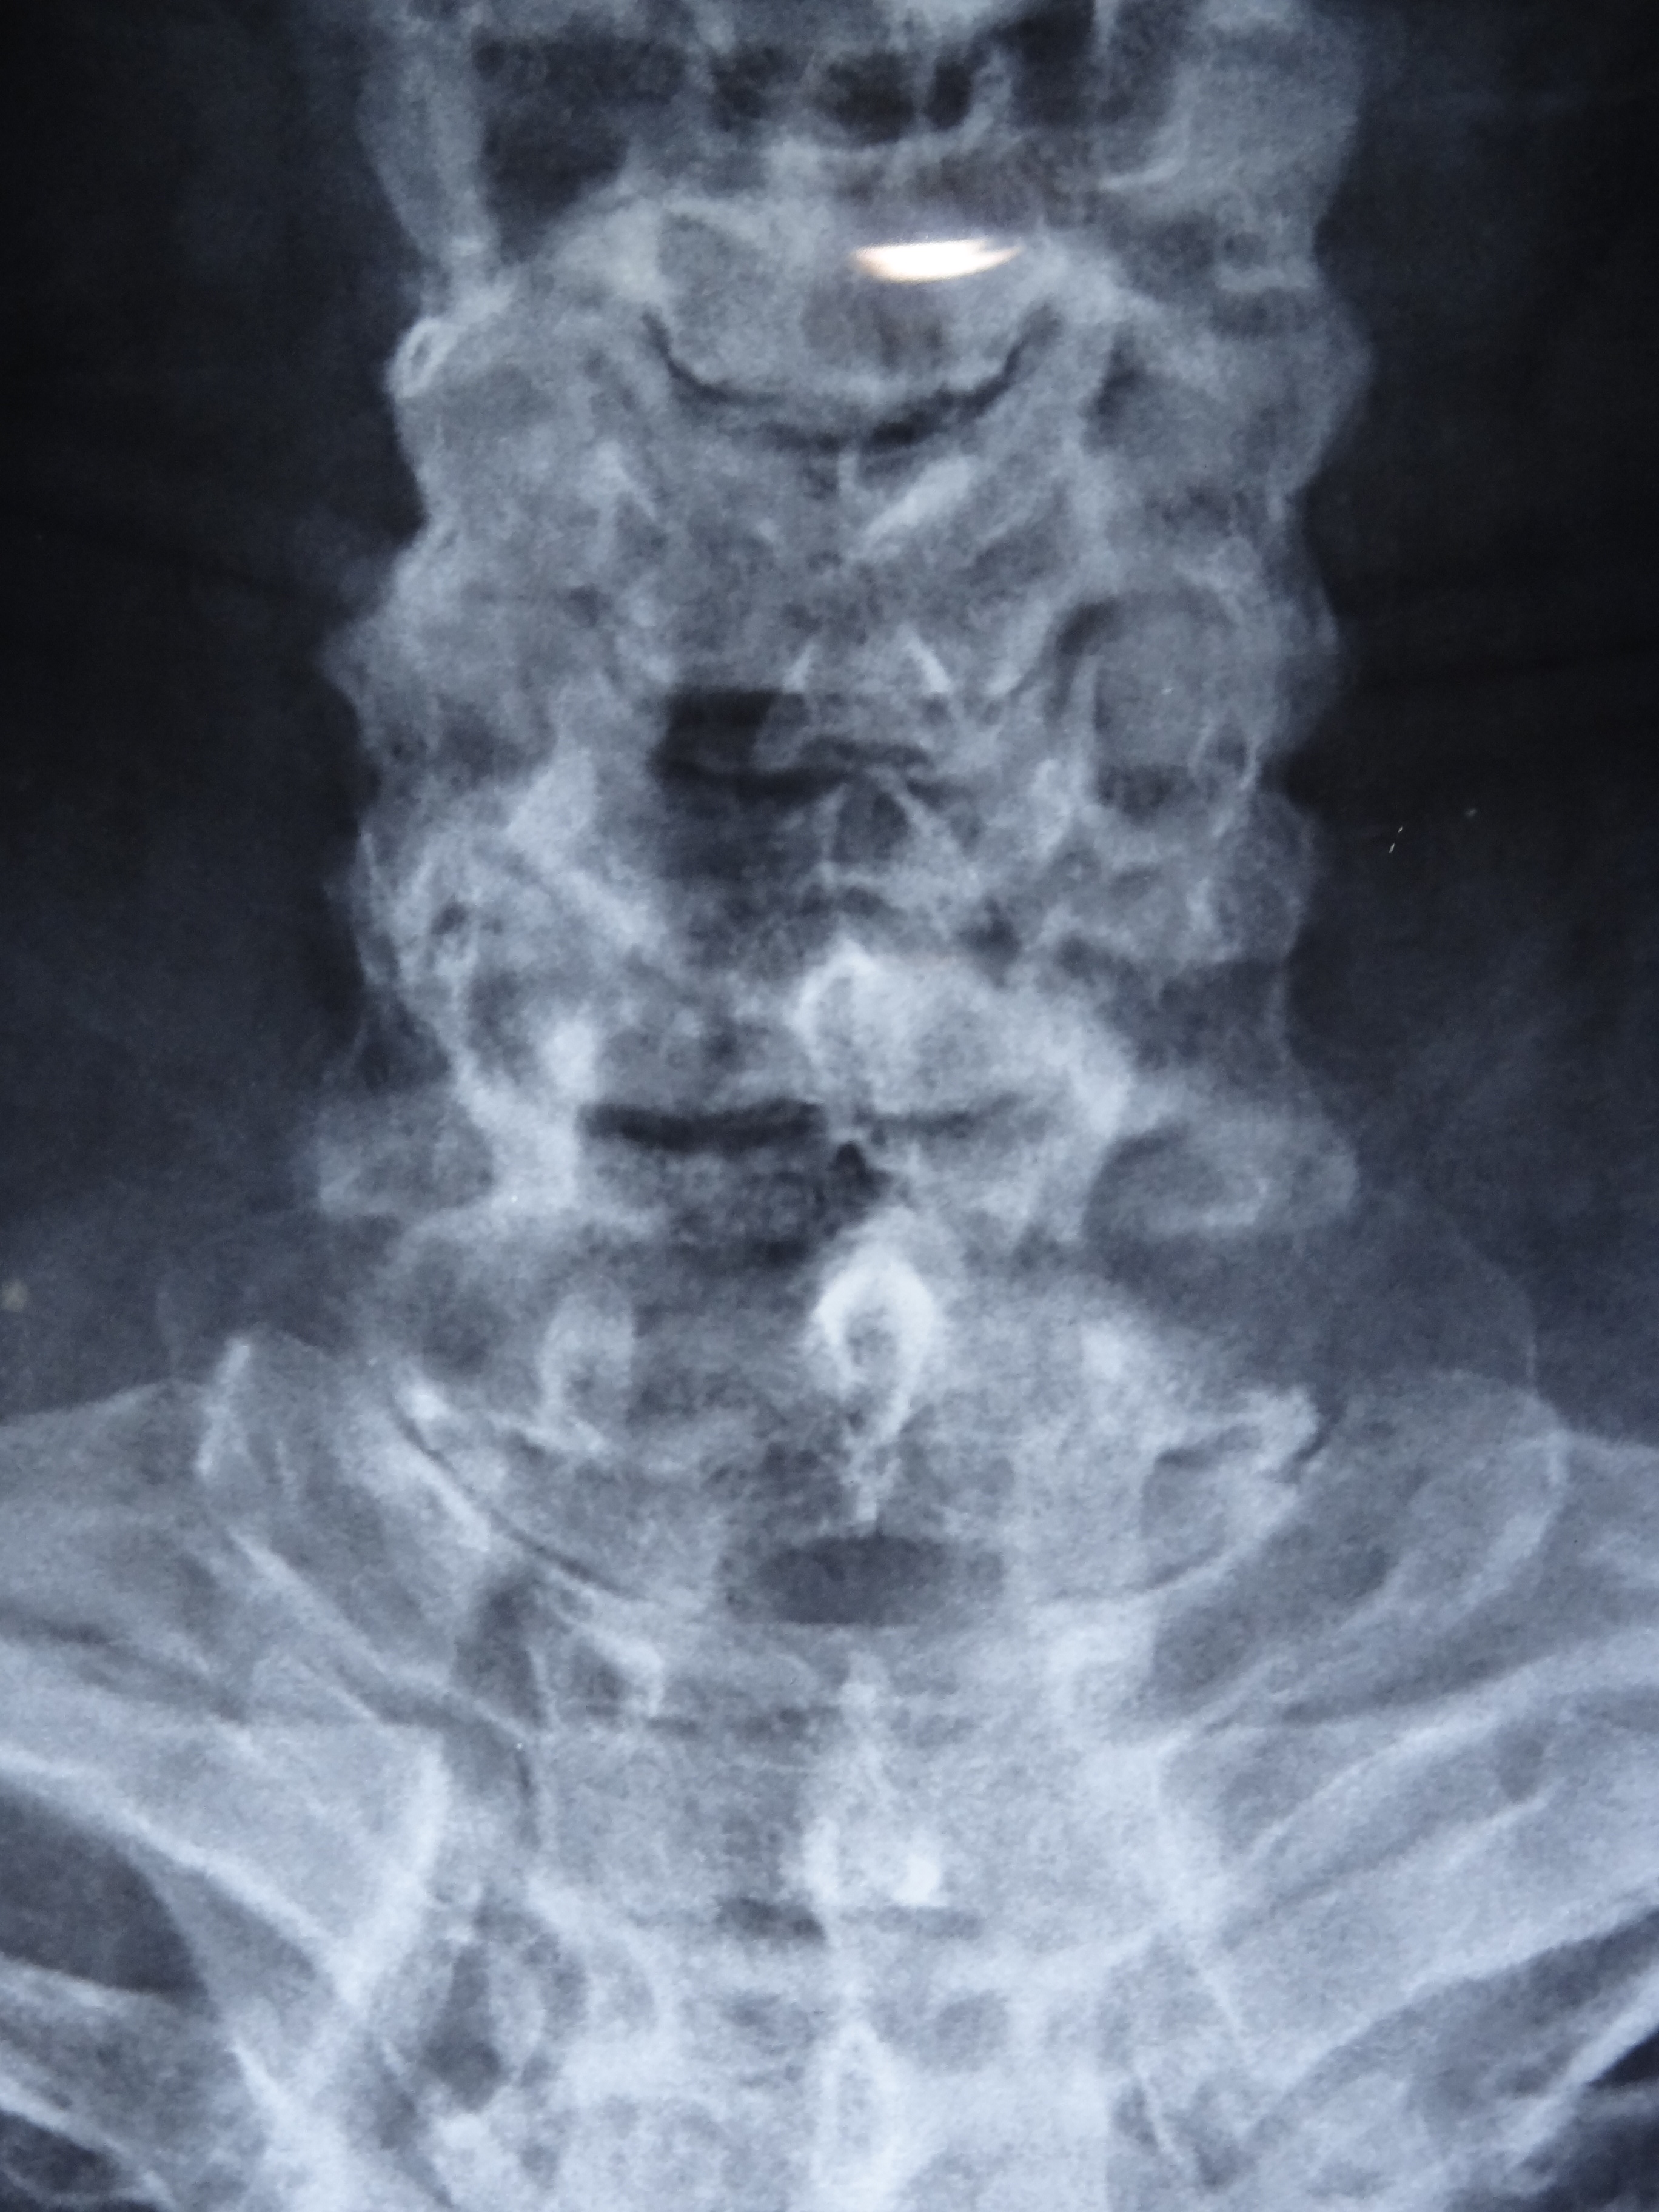

Forestier’s disease with complete spinal involvement

A 70-year-old diabetic and hypertensive male patient visited our clinic with complaints of non-inflammatory back pain since two years. He was heavy built with a BMI of 29 kg/m2. Physical examination revealed limitation of flexion, extension, and lateral flexion of lumbar spine. X-ray of spine revealed flowing calcification of anterior longitudinal ligaments from cervical to lumbar spine with claw osteophytes giving rise to characteristic ‘Melting Wax’ appearance (Panel A: fig A- cervical anteroposterior (AP), fig B- cervical lateral , fig C- lumbar AP , fig D- lumbar lateral) (Panel B: fig E- thoracolumbar AP, fig F- thoracolumbar lateral). Sacroiliac joints were normal (Panel A: fig C- white arrow). The diagnosis was diffuse idiopathic skeletal hyperostosis (DISH or Forestier’s disease) and symptomatic treatment was initiated.